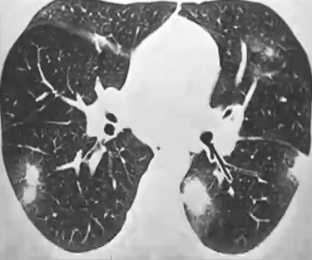

❖ 急性和亚急性期:单/双肺结节,伴/不伴双肺弥漫斑片影,常伴有纵隔和肺门淋巴结增大

❖ 亚急性期者斑片影更为局限

❖ 慢性期与结核相似:上叶多见的空洞、纤维化、肺体积缩小、胸膜增厚、淋巴结钙化(但不大)等